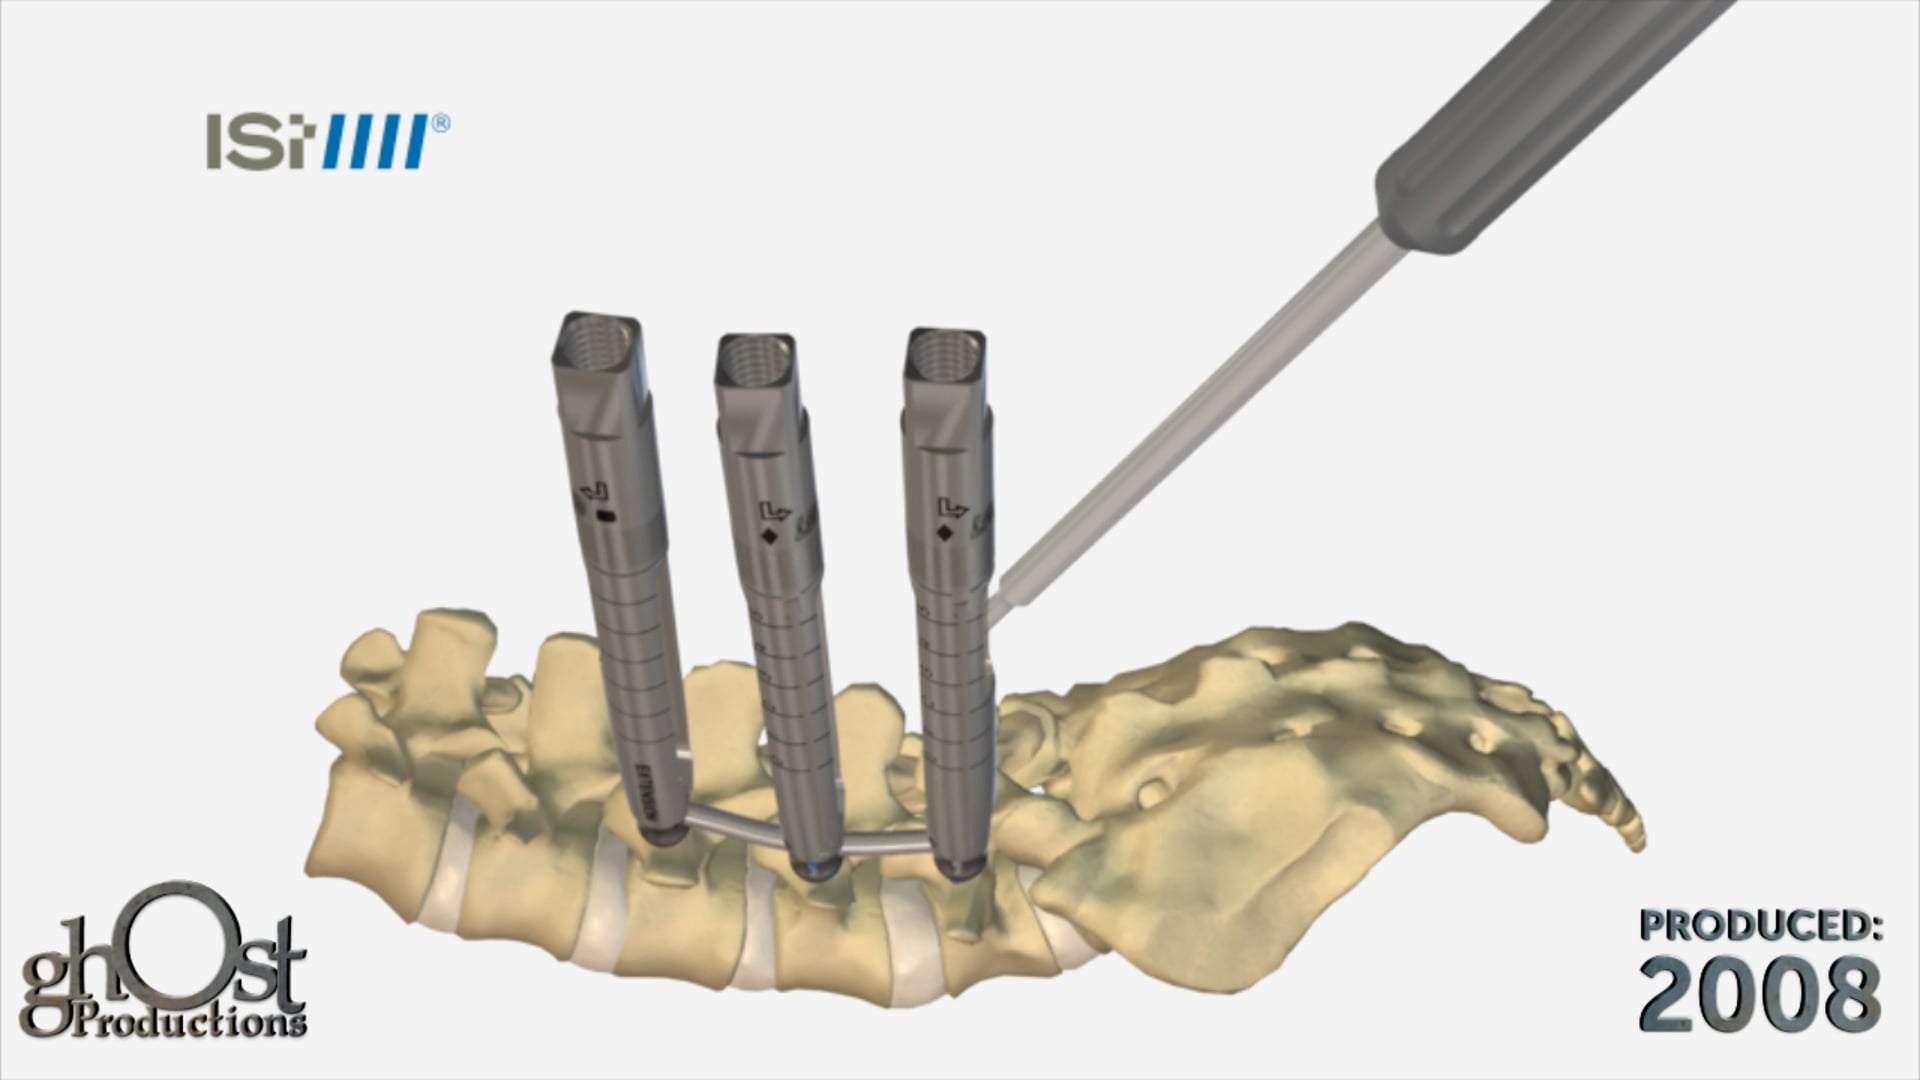

Ghost Productions showcases Biomet's ePAK DVR Crosslock Distal Radius plating system, designed to simplify treatment of distal radius fractures.

In this medical animation, created by Ghost Productions for Biomet, the innovative ePAK DVR Crosslock Distal Radius plating system is showcased. This cutting-edge product is designed to simplify the treatment of distal radius fractures, a common injury that can be challenging to address. The ePAK DVR offers advanced fixation options and streamlined instrumentation, making it easier for medical professionals to provide effective care to their patients. This animation is a valuable resource for anyone in the field of orthopedic medicine, and highlights the benefits of Biomet's state-of-the-art product.